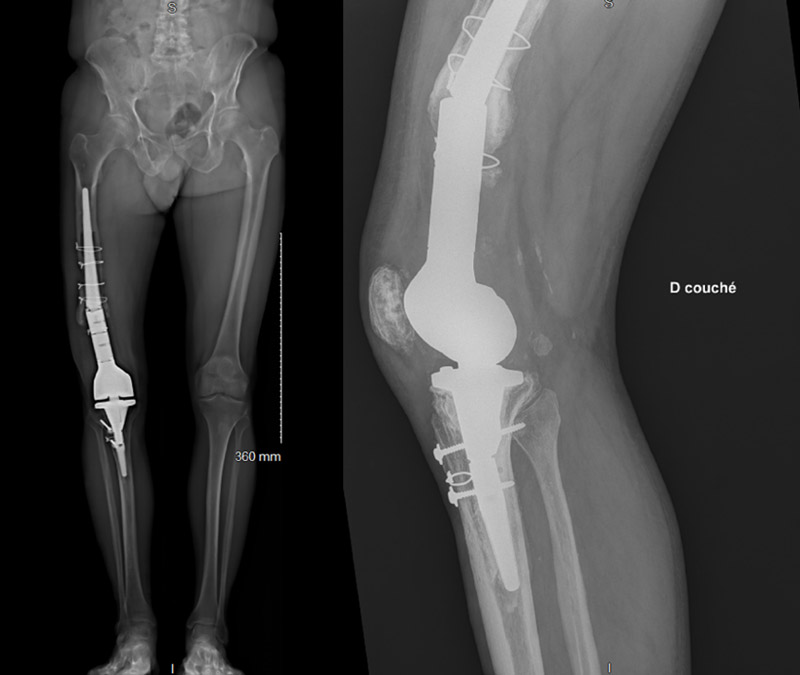

- 2006: proximal right tibia fracture, osteosynthesis with plates and screws

- 2008: persistent knee pain, distal femur giant cell tumor diagnosis: removal of the osteosynthesis materials and massive reconstructive knee prosthesis

- 2019: knee prosthesis revision for aseptic loosening, new custom-made massive reconstructive knee prosthesis

Major femoral osteolysis was noticed on distal femoral shaft until approximately the second steel strapping. This femoral height level was chosen to do the femorotomy. The remaining femoral stem was then tested and appeared to be perfectly sealed.

The appropriate size of the custom-made Implant RescueSleeve MEGASYSTEM-C (LINK® society) was then tested and chosen. The sleeve was cemented around the remaining femoral stem and fixed with 16 specific screws.

The prosthesis was then reconnected to the tibial component.